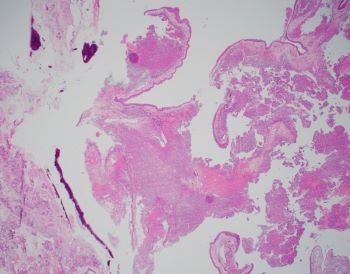

A 42-year-old female presents with nasal obstruction and a 3.0 cm polypoid nasal mass. The nasal mass shows cytologically bland spindle cell proliferation with scattered staghorn vessels and perivascular hyalinization. Provided are the H&E slides along with provided IHC including beta-catenin (tumor cells are diffusely and strongly positive for beta catenin nuclear staining, shown below) and SMA positivity (not provided). CD34 and STAT6 are negative.

Ahmed_Case_1.1_2023.jpg Ahmed_Case_2_2023.png